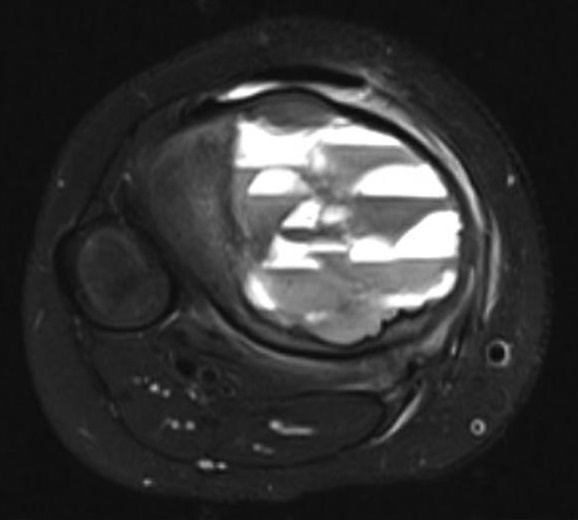

Welche Differentialdiagnose ist auf Grundlage des vorliegenden Röntgenbildes, der MRT-Befunde und der klinischen Informationen am wahrscheinlichsten? Anamnese: Schmerzhaftes Knie bei einem 6-jährigen Jungen.